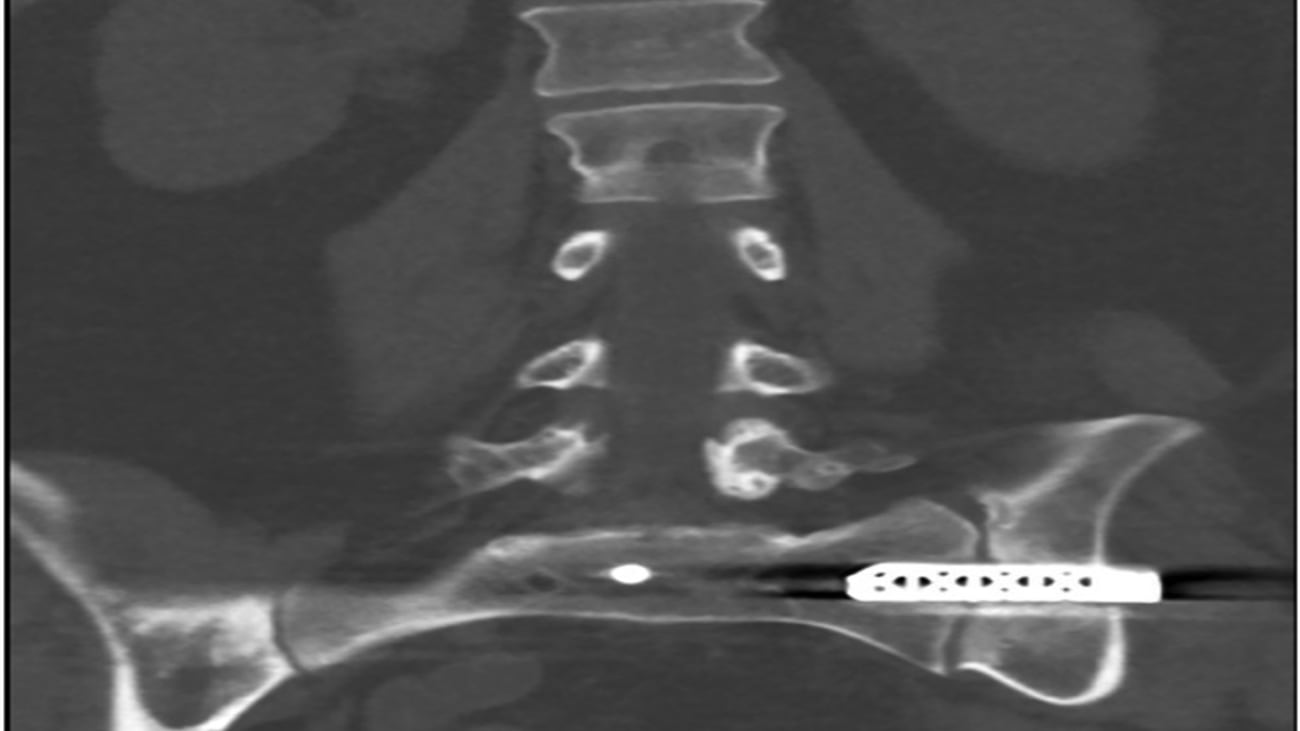

A paper recently published by UT Southwestern Medical Center’s Department of Orthopeadic Surgery discusses surgical management of Sacroiliac joint (SIJ) pain and the reported revision rates as they relate to the large proportion of MIS SIJ fusion procedures being done by non-surgery-trained specialists. An increasing number of these procedures are being performed with the expectation of more revisions and failed implants being referred to orthopedic surgeons and neurosurgeons for removal. The removal process of these implants often depends on the manufacturer’s removal set, whose technique guide is not readily available online in most instances. UT Southwestern orthopaedic surgeons have successfully applied an alternative removal technique to remove iFuse implants that limits bone loss and allows for additional control of blood loss and ease of bone graft application into the void left behind by the implant.